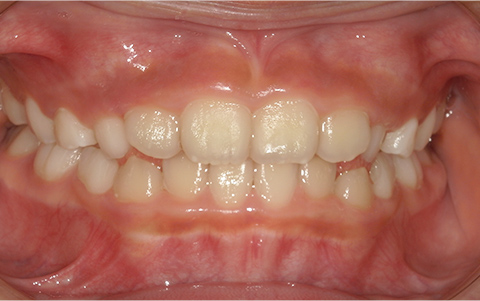

このような歯並びで

お悩みではないですか?

歯並びが悪い

症例